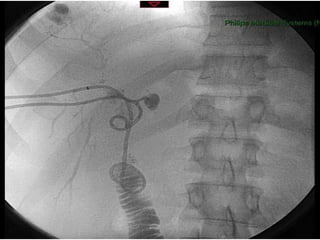

PATOGÊNESE  Isquemia Lesões complexas Strasberg E3-5, Bismuth>3 CT angio MRA Angiografia

PATOGÊNESE IsquemiaLesões complexas Strasberg E3-5, Bismuth>3 CT angio MRA Angiografia